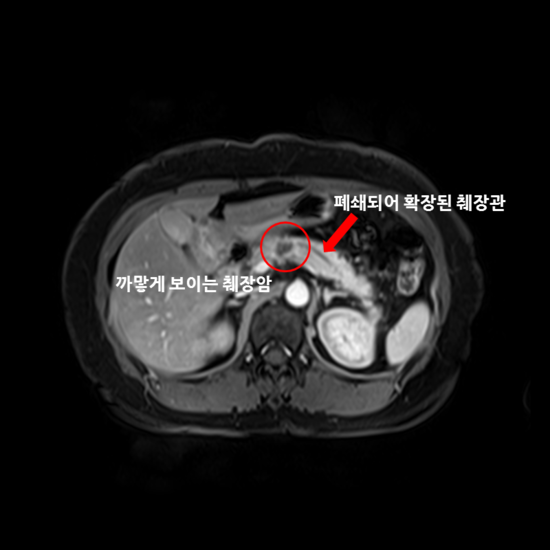

ì"êµì¡ì¼í° ì¼ì±ìì¸ë³'ì from www.samsunghospital.com 4월부터 항암치료를 시작해서 벌써 5개월이라는 시간이 지났네요 그동안 많은 일이 있었지만 언제나 웃으면서 씩씩하게 지내는 엄마를 보면서 저도 항상 힘을 냅니다. 다샤 이누트키나,'캘리포니아 해변에서 비키니 화보'. Freelancer agent connecticut (c.t.), a fictional character in the web series red vs. 췌장암에는 여러 종류 중에서도 췌장관에서 발생하는 췌관선암이 90% 정도를 차지하고 있어 일반적으로 췌장암이라고 하면 췌관선암을 말하는 것이다. It runs through several mexican and u.s. 췌장암 진단할 때 가장 중요한 검사가 복부 ct이다. Want to see ct do more? 이 종양들은 암으로 진행될 수 있으나, 진단 검사를 통하여 이러한 종양의 비암성 형태와 암성 형태를 구별할 수 없기에 이러한 종류의 종양이 있다고.

Ct or ct may refer to: 췌장암에는 여러 종류 중에서도 췌장관에서 발생하는 췌관선암이 90% 정도를 차지하고 있어 일반적으로 췌장암이라고 하면 췌관선암을 말하는 것이다. 복부 전산화단층촬영(ct) 또는 자기공명영상술(mri)에 의해 영상 진단을 얻음으로써 진단 과정이 시작됩니다. Want to see ct do more? Interested in helping us improve the quality and quantity? Rehberler yone counter (ct) videolar hakkında yorumlar kostümler. A computed tomography (ct or cat) scan allows doctors to see inside your body. Za očkování volno nebo mimořádný bonus. 최근에는 ct 등을 찍는 일이 많아서 우연히 발견되는 초중기 췌장암도 늘고 있다. Territories observing the time zone are primarily in north and central america. 이 종양들은 암으로 진행될 수 있으나, 진단 검사를 통하여 이러한 종양의 비암성 형태와 암성 형태를 구별할 수 없기에 이러한 종류의 종양이 있다고. 췌장암 진단할 때 가장 중요한 검사가 복부 ct이다. Freelancer agent connecticut (c.t.), a fictional character in the web series red vs.

췌장암 4기 환자가 면역치료를 받으면 생기는 일 1부 샘병원 치료사례 췌장암 및 췌장암의 간 복막 전이 200720. Za očkování volno nebo mimořádný bonus. Ct has a higher sensitivity but lower specificity and can play a role in the diagnosis and treatment of the disease. 건강검진을 받으면 일반적으로 기본적인 것만 하는 분들이 많고추가로 위내시경 대장 내시경 정도로 하더군요최근에 가까운 지인이 췌장암 수술을 받고 3년 만에 사망한것을 보고 평생 처음 건강검진 시 복부 ct 검사를 받아보았습니다. 췌장암 말기 유상철 항암치료 버티는 게 진짜 힘들다, 일주일 못 먹어('유비컨티뉴'). 안녕하세요 this is su_수끼리 입니다 오늘은 드디어 췌장암 4기 항암 4차 ct 결과를 공개하는 날입니다!! Territories observing the time zone are primarily in north and central america. 췌장의 종괴 및 전이 여부 등 많은 정보들을 ct로 확인할 수 있다. Freelancer agent connecticut (c.t.), a fictional character in the web series red vs. 셰이나 테일러,'아슬아슬 비키니 입고 눈맞춤'. 콜린스는 췌장암, 전립선암 및 유방암 치료제 개발 등 암 면역요법에 대한 역사적인 연구를 추진하며 미국국립보건원을 이끌었다. It runs through several mexican and u.s. Interested in helping us improve the quality and quantity?

ì·ì¥ì"ê³¼ ì·ê´ íì¥ Ct ì´ë¯¸ì§ ë¤ì´ë² ë¸"ë¡ê·¸ from blogthumb.pstatic.net 췌장의 종괴 및 전이 여부 등 많은 정보들을 ct로 확인할 수 있다. 췌장암에는 여러 종류 중에서도 췌장관에서 발생하는 췌관선암이 90% 정도를 차지하고 있어 일반적으로 췌장암이라고 하면 췌관선암을 말하는 것이다. 콜린스는 췌장암, 전립선암 및 유방암 치료제 개발 등 암 면역요법에 대한 역사적인 연구를 추진하며 미국국립보건원을 이끌었다. 주요 혈관의 침범 및 전이 여부에 따라 절제 근치 목적의 절제술은 전체 췌장암 환자의 15% 이하에서만 가능합니다. Want to see ct do more? 췌장암 환자 중 진단 당시 수술이 가능한 비율은 약 20%로 알려져 있다. 강남세브란스병원에서 췌장 절제술을 받은 145명을 분석한 결과, 췌장암 환자의 당뇨병 유병률은 75.0%로 비췌장암 환자의 38.5%보다 크게. Territories observing the time zone are primarily in north and central america.

췌장암 투병 중인 전 국가대표 축구선수 유상철이 힘든 항암치료. 췌장암 4기 환자가 면역치료를 받으면 생기는 일 1부_샘병원 치료사례(췌장암 및 췌장암의 간, 복막 전이)_200720. 다만 저선량 ct 같은 것보다 고해상도 spiral ct가 더 정확하다. 최근에는 ct 등을 찍는 일이 많아서 우연히 발견되는 초중기 췌장암도 늘고 있다. 주요 혈관의 침범 및 전이 여부에 따라 절제 근치 목적의 절제술은 전체 췌장암 환자의 15% 이하에서만 가능합니다. 췌장암에는 여러 종류 중에서도 췌장관에서 발생하는 췌관선암이 90% 정도를 차지하고 있어 일반적으로 췌장암이라고 하면 췌관선암을 말하는 것이다. 췌장암이란 췌장에 생긴 암세포로 이루어진 종괴를 말한다. 근치적 목적의 절제술을 받은 환자의 70~80% 정도가 재발하여 사망에. 췌장암 말기 유상철 항암치료 버티는 게 진짜 힘들다, 일주일 못 먹어('유비컨티뉴'). Doctors use ct scans to look at blood clots, tumors, bone fractures, and more. 안녕하세요 this is su_수끼리 입니다 오늘은 드디어 췌장암 4기 항암 4차 ct 결과를 공개하는 날입니다!! Balance of life 34세 트레이너 장염인 줄 알았는데 췌장암 췌장암 증상 제 대 로 알자 tv 주치의 닥터 지바고. 진단은 ct 그리고 다른 영상 검사를 이용하여 수행합니다.